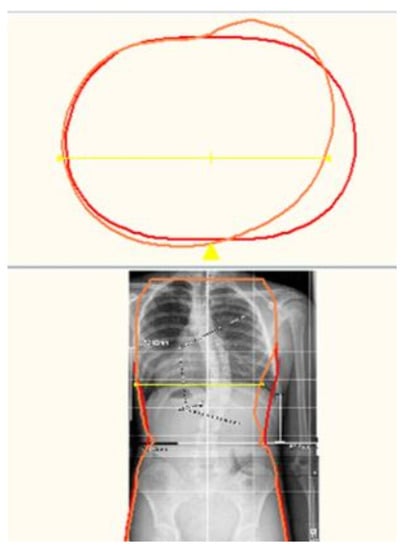

All Boston Brace 3D orthoses are custom-fabricated from a scan of the patient (Figure 3). The scanned image (Figure 4) is imported into the CADCAM (Rodin4D) program and is modified according to the Boston Brace 3D principles that include internal pushes and shifts with opposite areas of reliefs. The dimensions of each component are determined by the clinical exam and X-ray blueprint. Internal forces are oriented to provide an anterior/medially resultant vector while maintaining the individual’s overall sagittal balance. This modification process results in an asymmetrical model of the patient, over which the brace is fabricated.

Figure 4. CAD model of a Boston Brace 3D orthosis.

Similar to the original Boston Brace System, the Boston Brace 3D is a systematic approach that includes a comprehensive clinical exam of each patient and blueprint of the radiograph, with the results of each dictating the specific brace design. A scan of the patient is taken (Figure 3). The scanned image (Figure 4) is imported into the CADCAM program for custom modification, which includes specific pushes and shifts to the model.

The scan is then modified according to the Boston Brace 3D principles, which include internal pushes and shifts opposite to the areas of reliefs, the dimensions of which are determined by clinical exam and X-ray blueprint. The internal forces are oriented to provide an anterior/medially resultant vector while maintaining the individual’s overall sagittal balance. Figure 5 shows a before-and-after modification model of a patient. Figure 6 provides a top-down transverse plane view through the apex of a right thoracic curve and shows the internal shift and push applied with the opposing area of relief. This modification process results in an asymmetrical model of the patient over which the brace is fabricated.